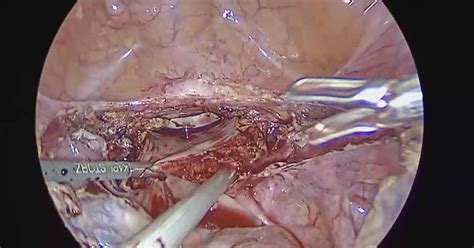

The surgery is execute under general anesthesia. The surgeon makes small prick in the abdomen, through which a laparoscope (a thin tubing with a camera) and specialized surgical instruments are inserted. The uterus is then detach and removed, either through the vagina or by being broken down into small-scale piece (morcellation) and removed through the small abdominal incisions.